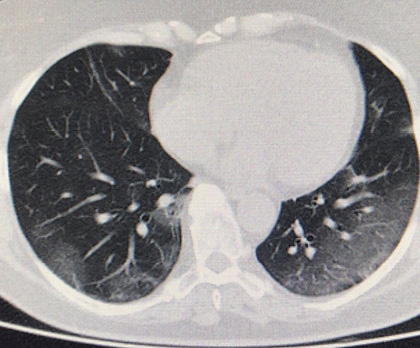

Routine clinical laboratory assays were performed in the hospital’s clinical laboratories. Clinical and laboratory information was extracted from the patients’ medical records. C reactive protein (CRP) in plasma was measured by immunoturbidimetry (Beckman Coulter, Krefeld, Germany). Interleukin-6 (IL-6) levels in plasma were measured by electrochemiluminescence (Siemens Medical Solutions Diagnostics, Siemens Healthcare, Erlangen, Germany). CT scans were read by experienced radiologists who scored results by severity using the criteria shown in Figure 1.

Figure 1. Clinical assessment of pneumonia severity based on computed tomography (CT) scores.

Scoring method: Mild (CT-1)—no more than three ground-glass opacities of <3 cm maximum diameter. Moderate (CT-2)—more than three ground-glass opacities; less than 50% involvement by visual assessment. Medium-heavy (CT-3)—ground-glass opacities and pulmonary consolidation; 50-70% involvement by visual assessment. Severe (CT-4)—diffuse ground-glass opacities with or without consolidation; more than 75% involvement by visual assessment.